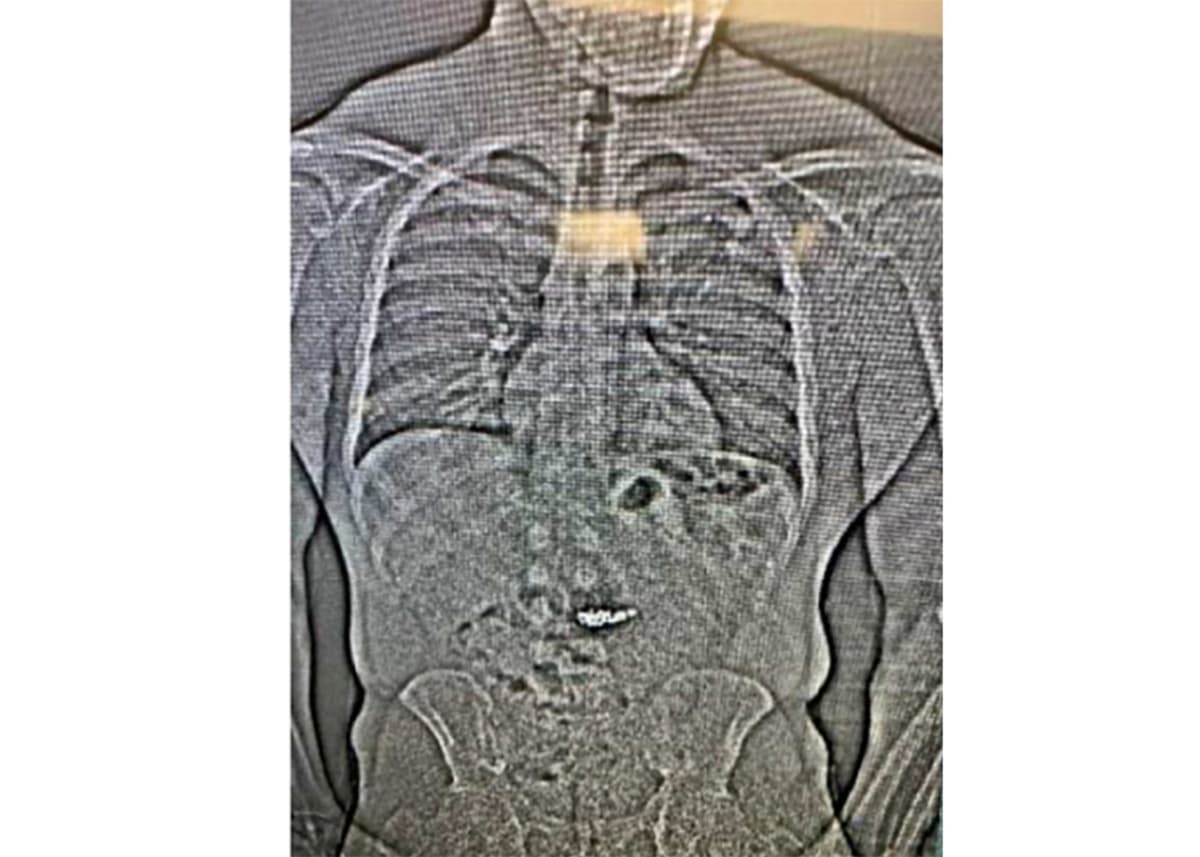

When the police later arrested him the same day, he was seen "swallowing several objects believed to be the stolen earrings". In custody, the man then asked the staff: "Will I be prosecuted for what's in my stomach?"

For two weeks, the man was monitored at a hospital where the police were finally able to secure all four earrings on March 12.